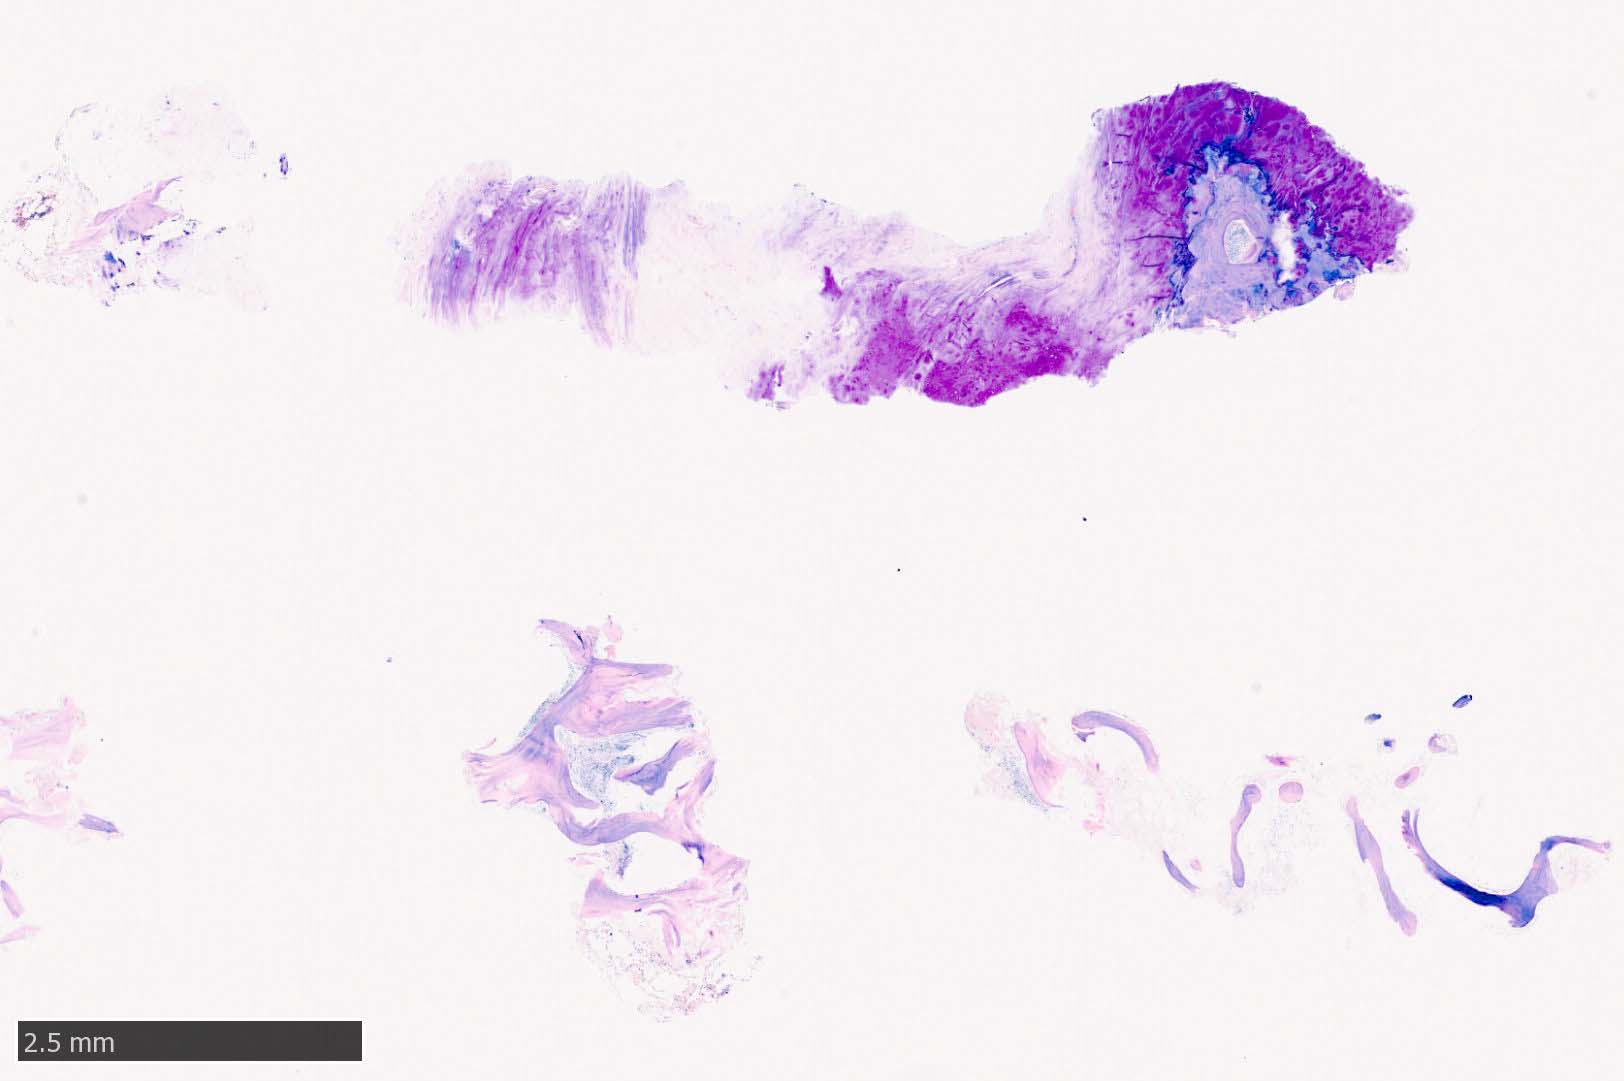

骨髄生検組織所見

骨髄生検組織では骨梁間に壊死に陥った細胞の凝固壊死像が確認できる. 本例では脂肪細胞は消失せず形態が残っている.壊死のあとには, 髄腔に線維化をきたす. 上図には線維化を示し, 右端の図では壊死巣と線維化の境界が観察される.

本例ではviableな腫瘍細胞がハーバース管と考えられる管内に認められた.(髄腔とハーバース管腔は解剖学的に同じ場所といえるのか?)

ハーバース管は緻密骨内の骨構造であり, 管内には動静脈, 脈管周囲リンパ管, 神経線維が入る. 解剖学的に海綿骨骨髄腔とは異なる空間構造と考えられる.--viableな腫瘍細胞の存在はリンパ管、血管内への腫瘍浸潤と考えられる.